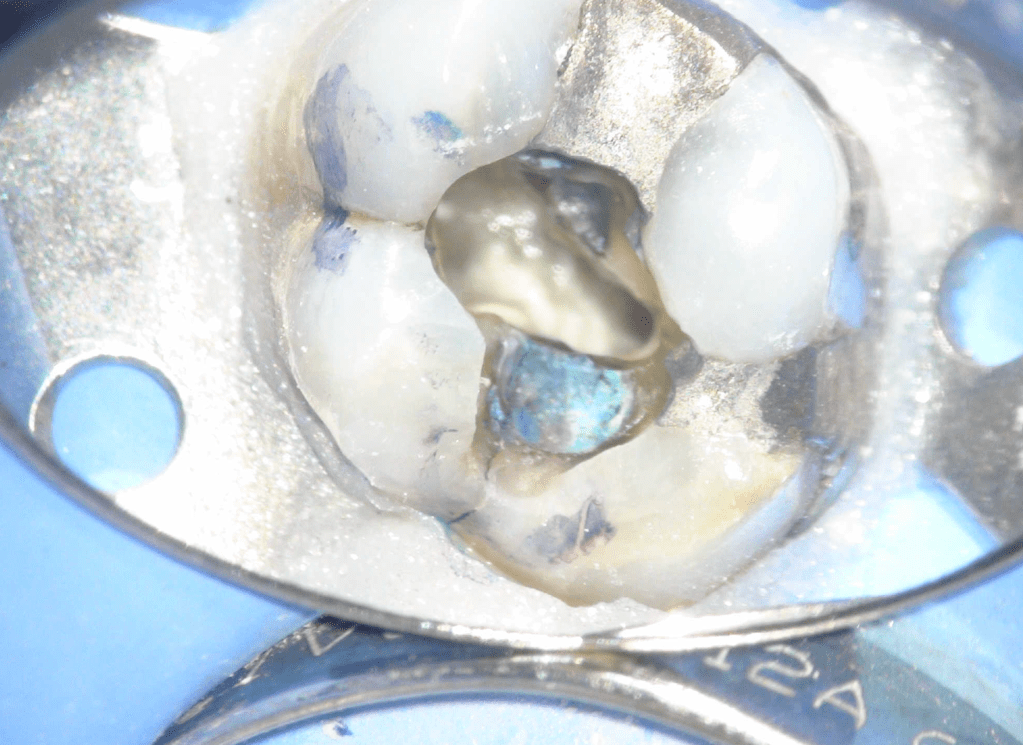

Fisura, remoción amalgama para explorar